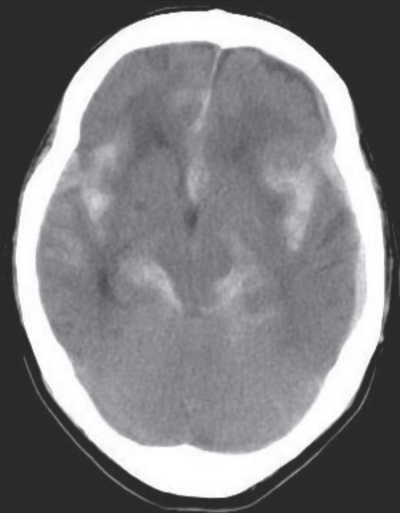

初診時に撮影した頭部単純CTを別に示す。入院後、ICUに入室して保存療法で経過を観察した。翌日の所見は以下のとおりであった。